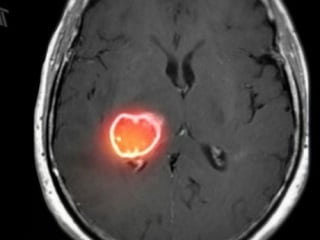

Диагностика

Основной способ диагностировать опухоль в головном мозге — выполнить компьютерную томографию (КТ) или магнитно-резонансную томографию (МРТ). В процессе операции также используется МРТ: это помогает контролировать процесс удаления узлов.

Иногда астроцитома головного мозга диагностируется с привлечением дополнительного метода — магнитно-резонансной спектроскопии (МРС). Это дает возможность провести биохимический анализ тканей опухоли и выявить состояние новообразования.